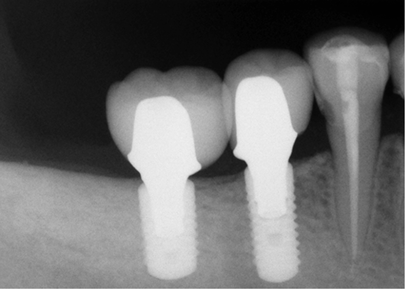

Sustituye los dientes que se han perdido con el paso de los años devolviendo funcionalidad y estética a tu boca.Un implante dental es un cilindro con forma de raíz dental fabricado de Material aloplástico (generalmente titanio) que se implanta quirúrgicamente debajo de las encías dentro del hueso maxilar o mandibular; una vez colocados y osteointegrado, el odontólogo colocara sobre ellos las coronas o puentes fijos que sustituirán a las piezas dentales perdidas, entonces el implante nos sirve para proveer retención y soporte a una prótesis dental fija o removible.

El Implante Dental se fusiona con el hueso de la mandíbula creando así un soporte estable para los dientes postizos, las prótesis, los puentes y las coronas individuales colocados sobre los implantes no se moverán dentro de la boca, proporcionando comodidad y seguridad a la hora de masticar y hablar.